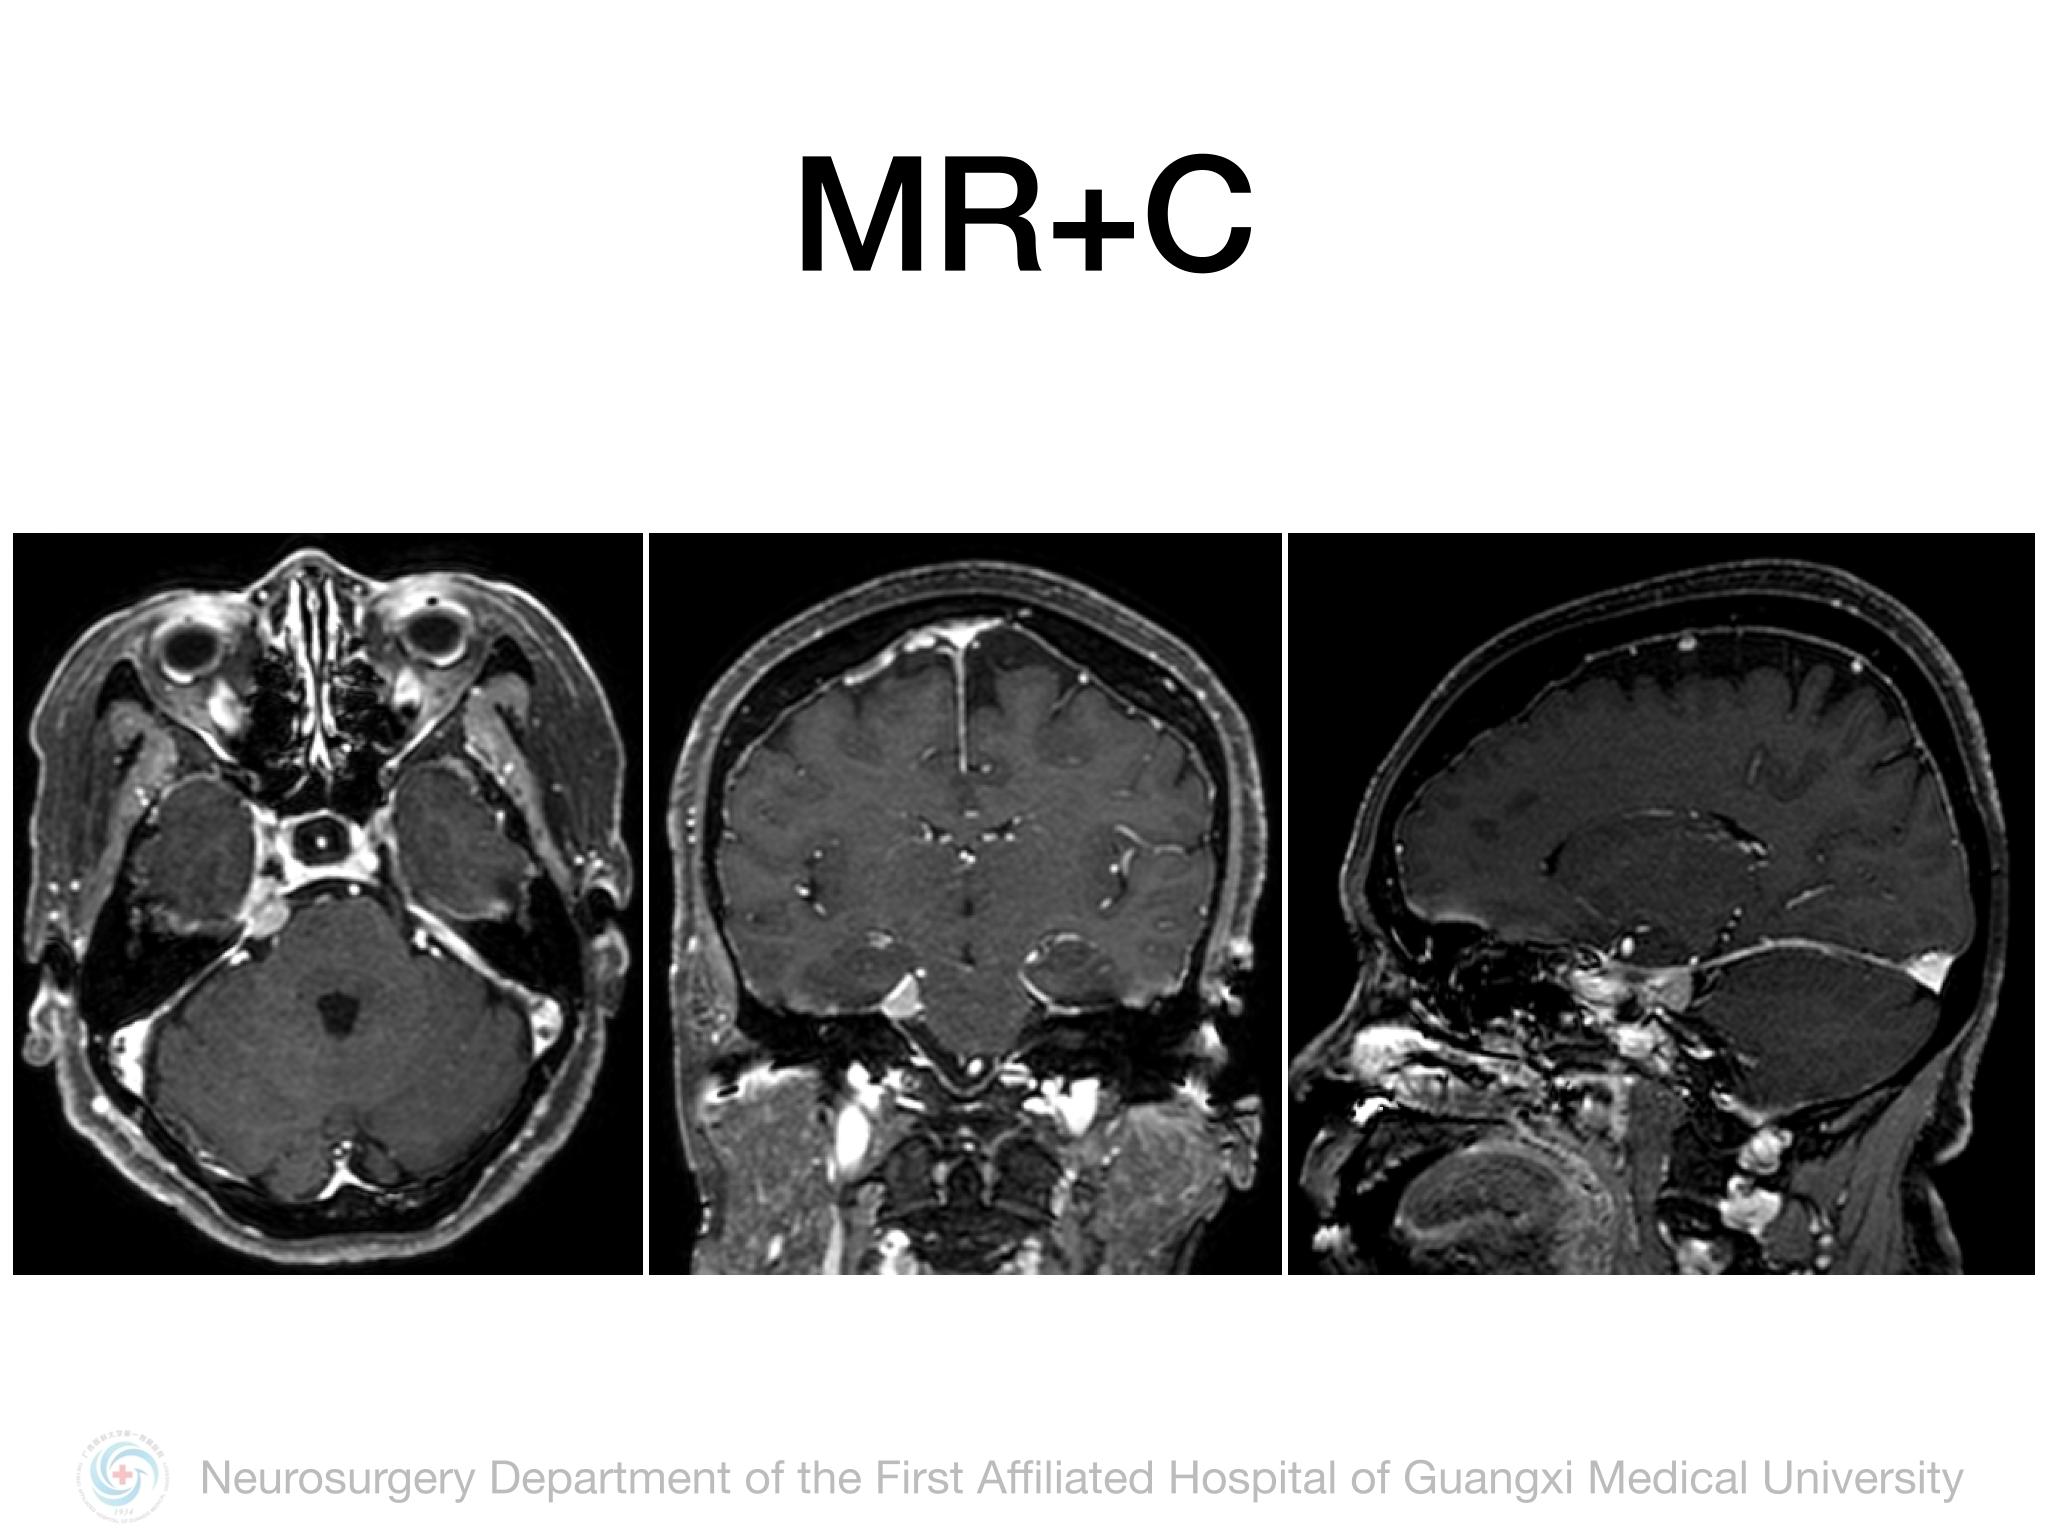

Meckel’s cave(MC)由多层硬膜围绕三叉神经半月结构成,通过三叉神经门与后颅窝蛛网膜下腔相通,起源于MC的脑膜瘤并不常见,文献报道约占所有颅内脑膜瘤的1%。Samii教授报道将MC脑膜瘤分4型,I型:局限于MC;II型:MC脑膜瘤向中颅窝扩展或海绵窦浸润;III型:MC脑膜瘤向CPA区扩展;IV型:MC脑膜瘤向中后颅窝均有扩展。本例属于I型,局限于MC,因此首选颞下经天幕入路,结扎岩上窦,显露部分岩尖,必要时硬膜下磨除岩尖。术中需注意颞叶及Labbe静脉壁保护,避免损伤岩静脉,尽可能全切肿瘤及基底。本例术中见肿瘤基底位于MC外侧壁及顶壁,主体位于MC,向后下推挤三叉神经,向后颅窝有部分延伸,但与脑干无黏连,向三叉神经内侧进入MC内侧空间,充分显露MC后将肿瘤及其基底全切,周围神经血管保护良好,术后无新发神经功能障碍,疗效满意。